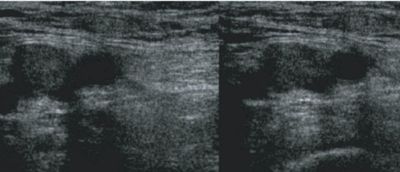

Abnormal

- Each segment of vein identified must be assess as compressible and noncompressible

- Touching of the anterior and posterior walls indicates a normal exam

- No touching with pressures sufficient to deform the artery indicates DVT